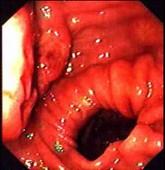

问题 患者,男,16岁,反复发热、消瘦1月,查体:心肺腹无阳性体征。电子胃镜图片如下,诊断为 ( )

选项 A.胃癌 B.胃淋巴瘤 C.胃溃疡 D.胃溃疡并真菌感染 E.克罗恩病

答案 B